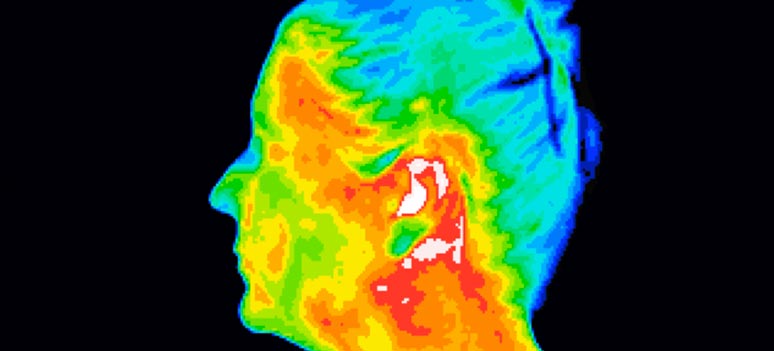

Medicinsk Thermografi: Inflammation – kroppens råb om hjælp

De fleste livsstilssygdomme starter med inflammation. Inflammation er kroppens egen forsvarsmekanisme, som er nødvendighed for at opretholde og reparere kroppens funktioner. Det er dybest set en god ting. Bare tænk på når vi får et bistik eller vrider om på anklen, så hæver det op, bliver varmt og rødt, og det gør ondt. Det er […]